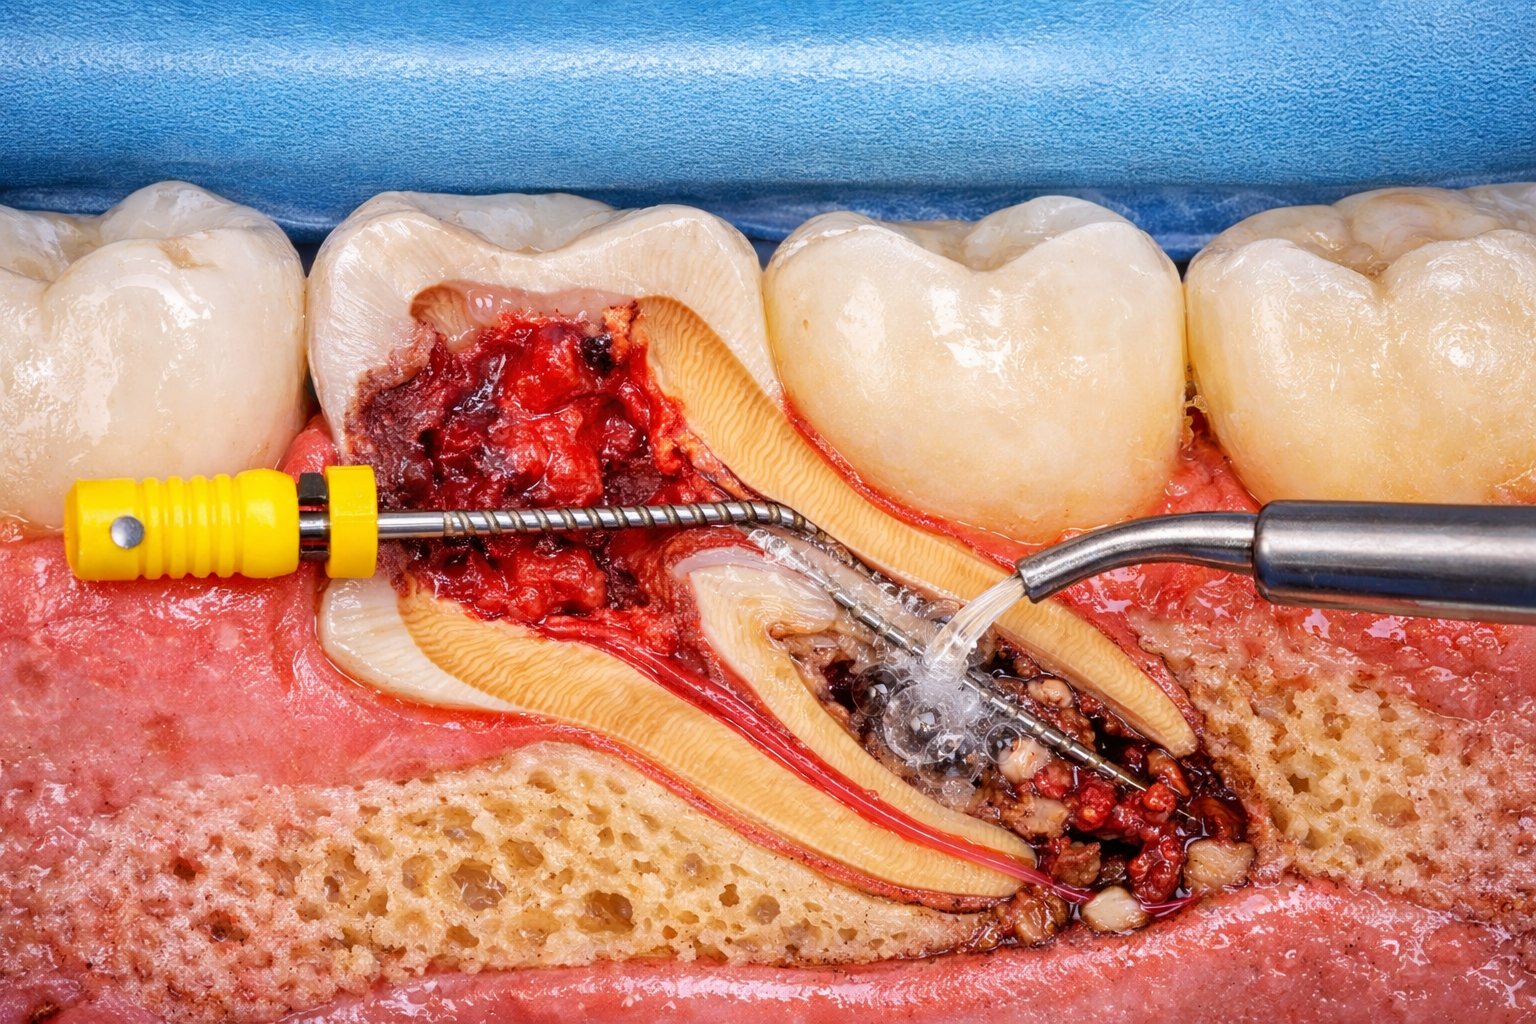

At Shree Balaji Maxillofacial Surgery & Dental Care, we offer

comprehensive Dental Services in Moradabad using advanced

technology and expert care. Our Dental Services in Moradabad

cover everything from preventive checkups to advanced treatments,

ensuring personalized care and long-term oral health for every patient.